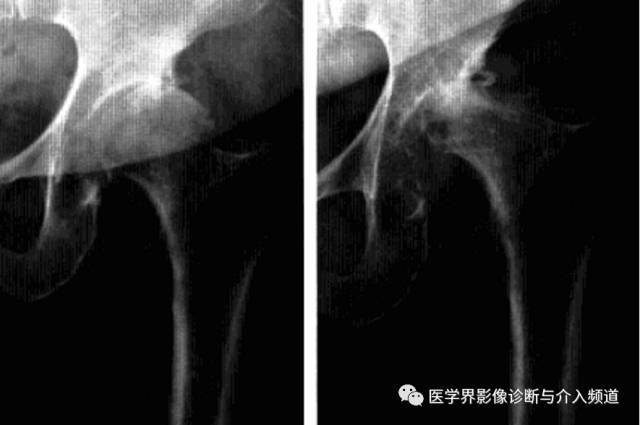

1、平片:髋关节间隙进行性消失是本病特征;早期股骨头无明显变化,数月间股骨头上方进展性破坏吸收,股骨头变扁,无囊变,骨赘增生不显著,周围软组织无明显异常。